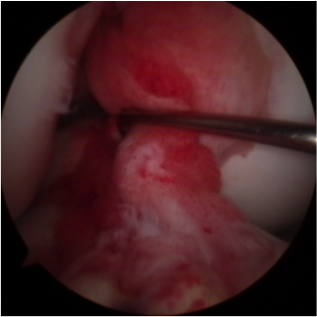

1年後の靭帯の状態